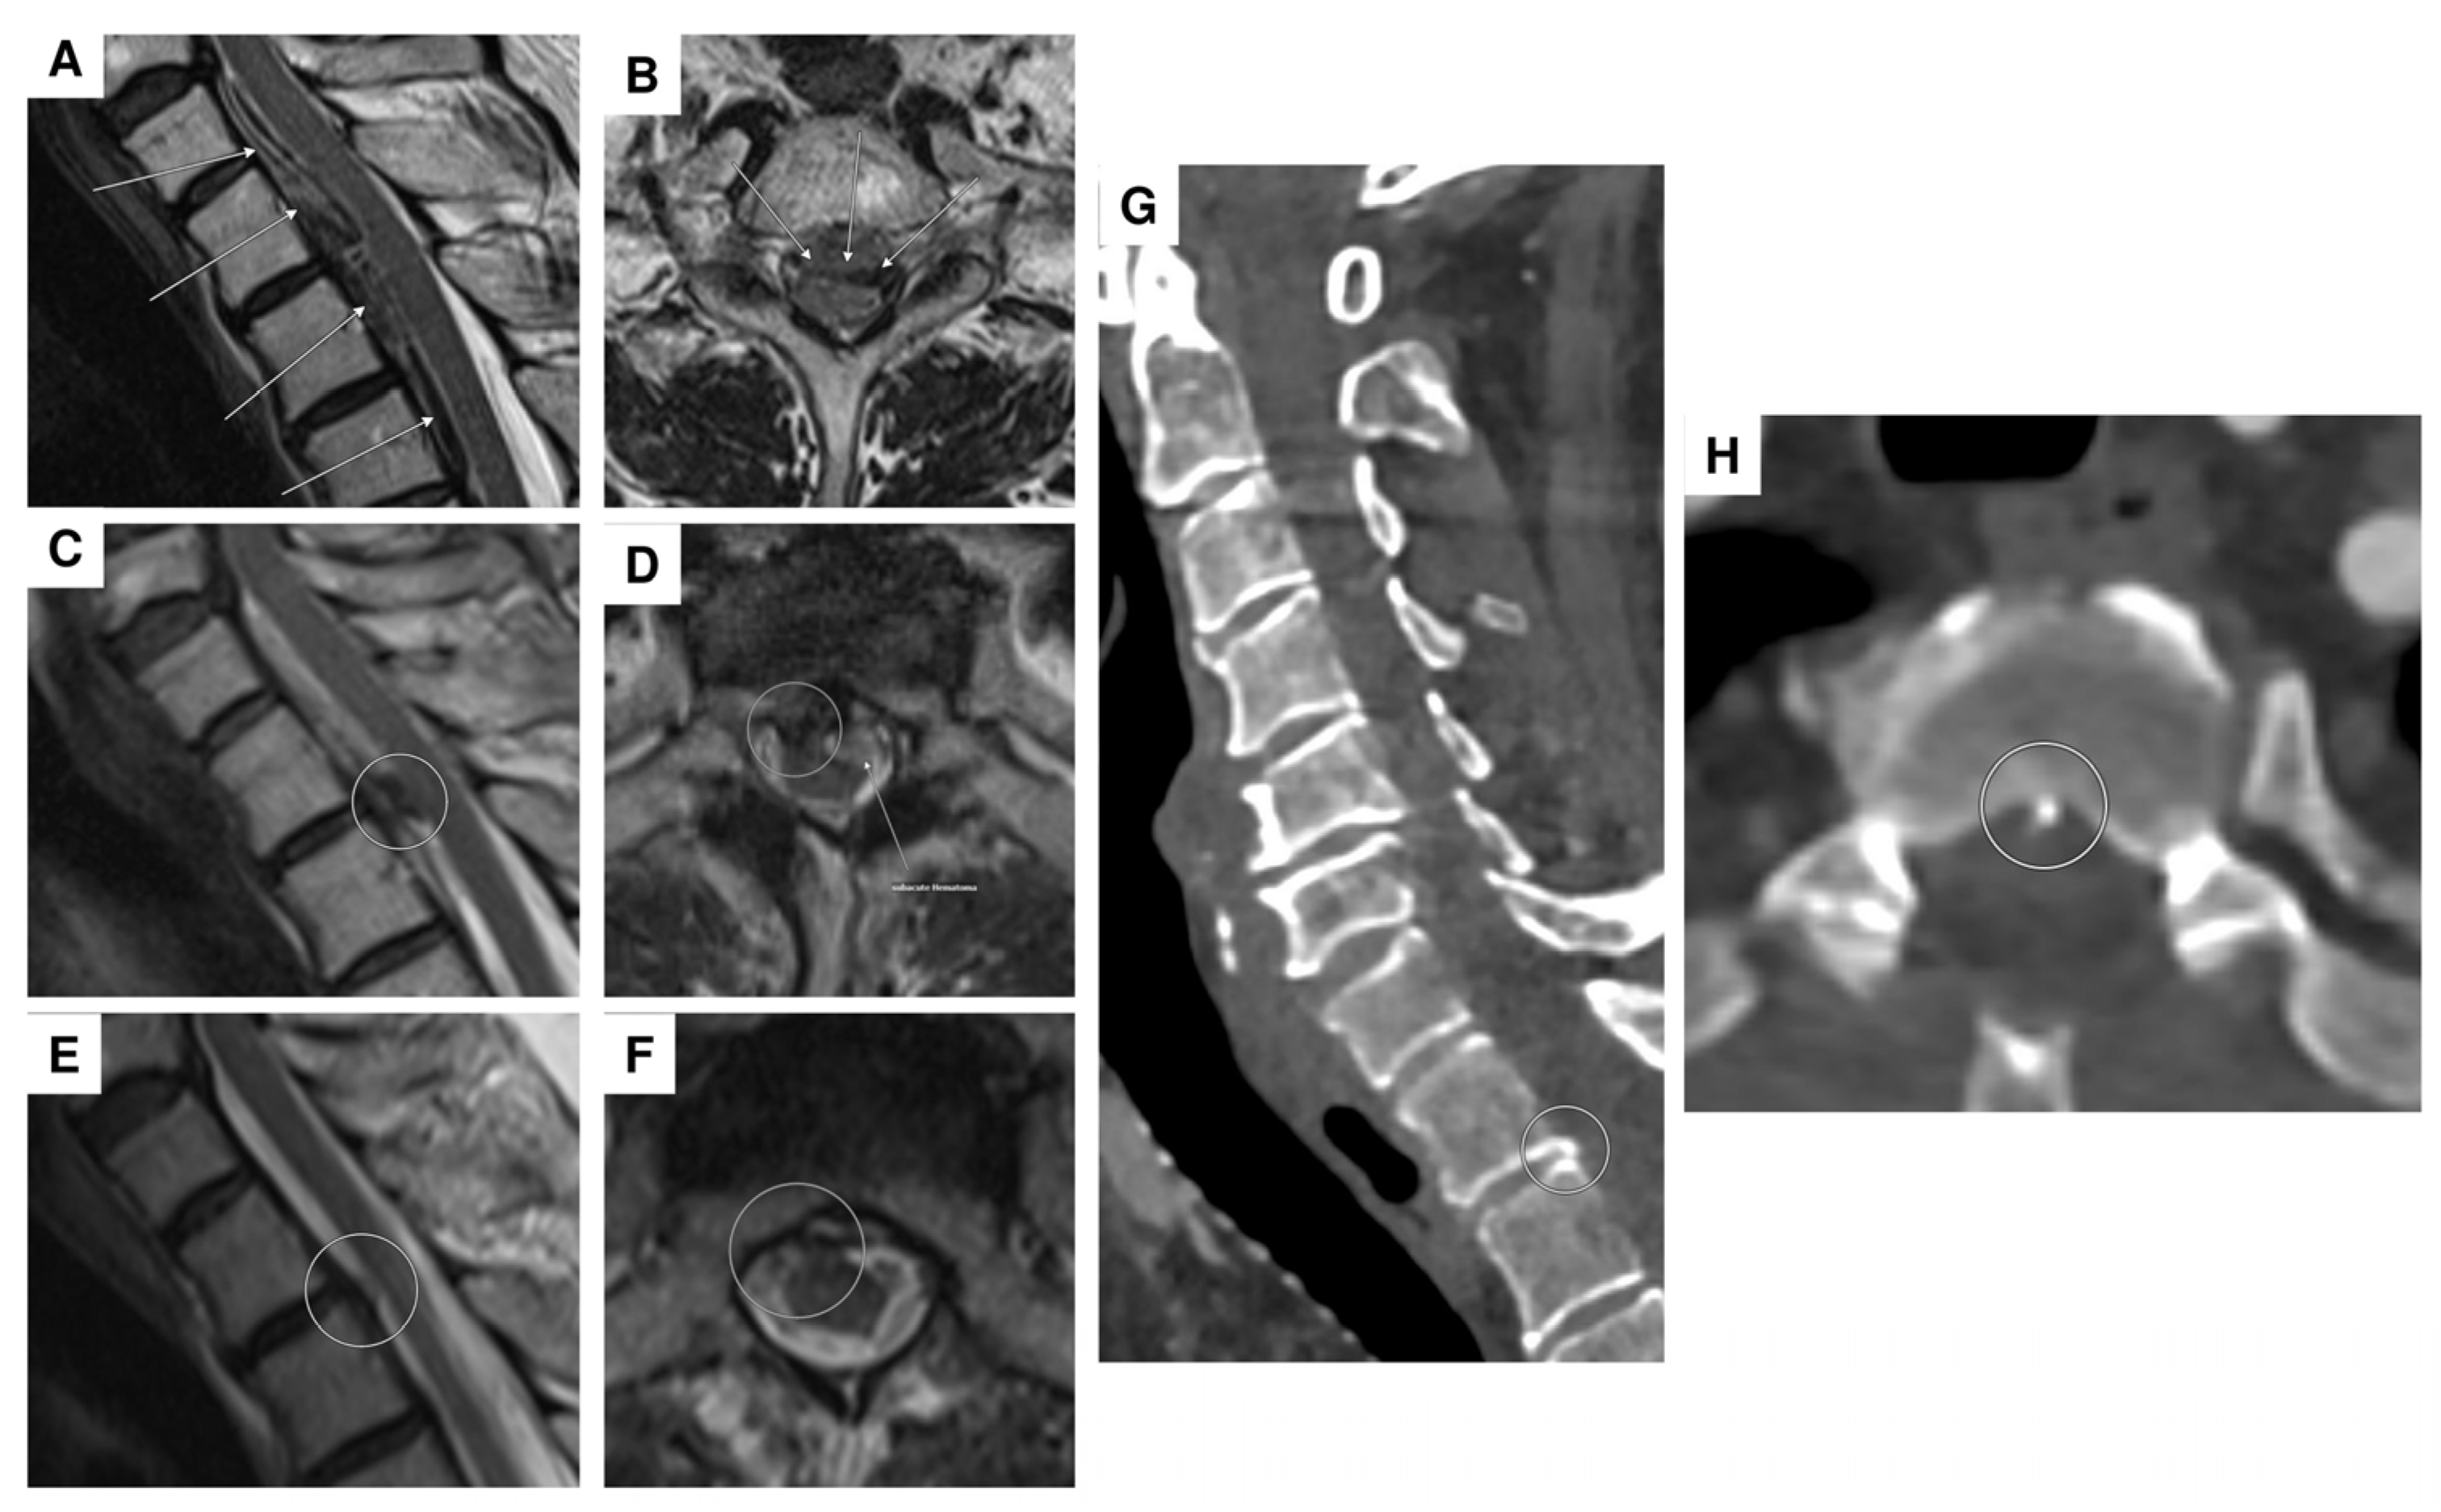

| 4 | F | 86 | iliosacral pain, paraparesis of the legs, and hypoesthesia from T11 | no evidence of manifest paralysis, intact sensation, unavailable reflexes in the lower extremities | spinal SAH; initially suspected T11 aneurysm; angiographically, no evidence of an aneurysm (spot sign) | anticoagulation (apixaban) | 2 lumbar punctures, repeated abdominal/thoracic CTA, DSA | conservative |

| 5 | F | 73 | headaches and pain in the back/neck pain | pronounced paraparesis of both legs | spinal SAH; angiographically, no evidence of an aneurysm | anticoagulation (rivaroxaban) | abdominal/thoracic CTA, multiple DSA, multiple spinal MRI | surgical procedure (evacuation of an intradural hematoma) |

| 6 | M | 55 | pain between the shoulder blades and the cervical spine, tingling sensations in all four extremities | tingling sensations in all extremities, unable to lift the legs, weakness in both arms | epidural bleeding and spinal SAH; suspected perimedullary aneurysm at T1/2; angiographically, no evidence of an aneurysm, epidural bleeding may be due to a microspur at T1/2 | microspur | multiple DSA, multiple spinal MRI | surgical procedure (evacuation of an epidural hematoma), then conservative (no evidence of an aneurysm) |